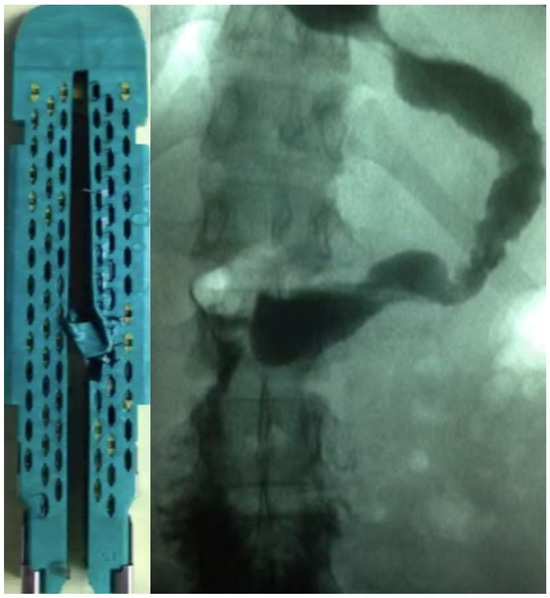

Successful Management of Gastric Leakage Post Gastric Sleeve by Gastric Bypass Conversion

2. Detailed Case Description